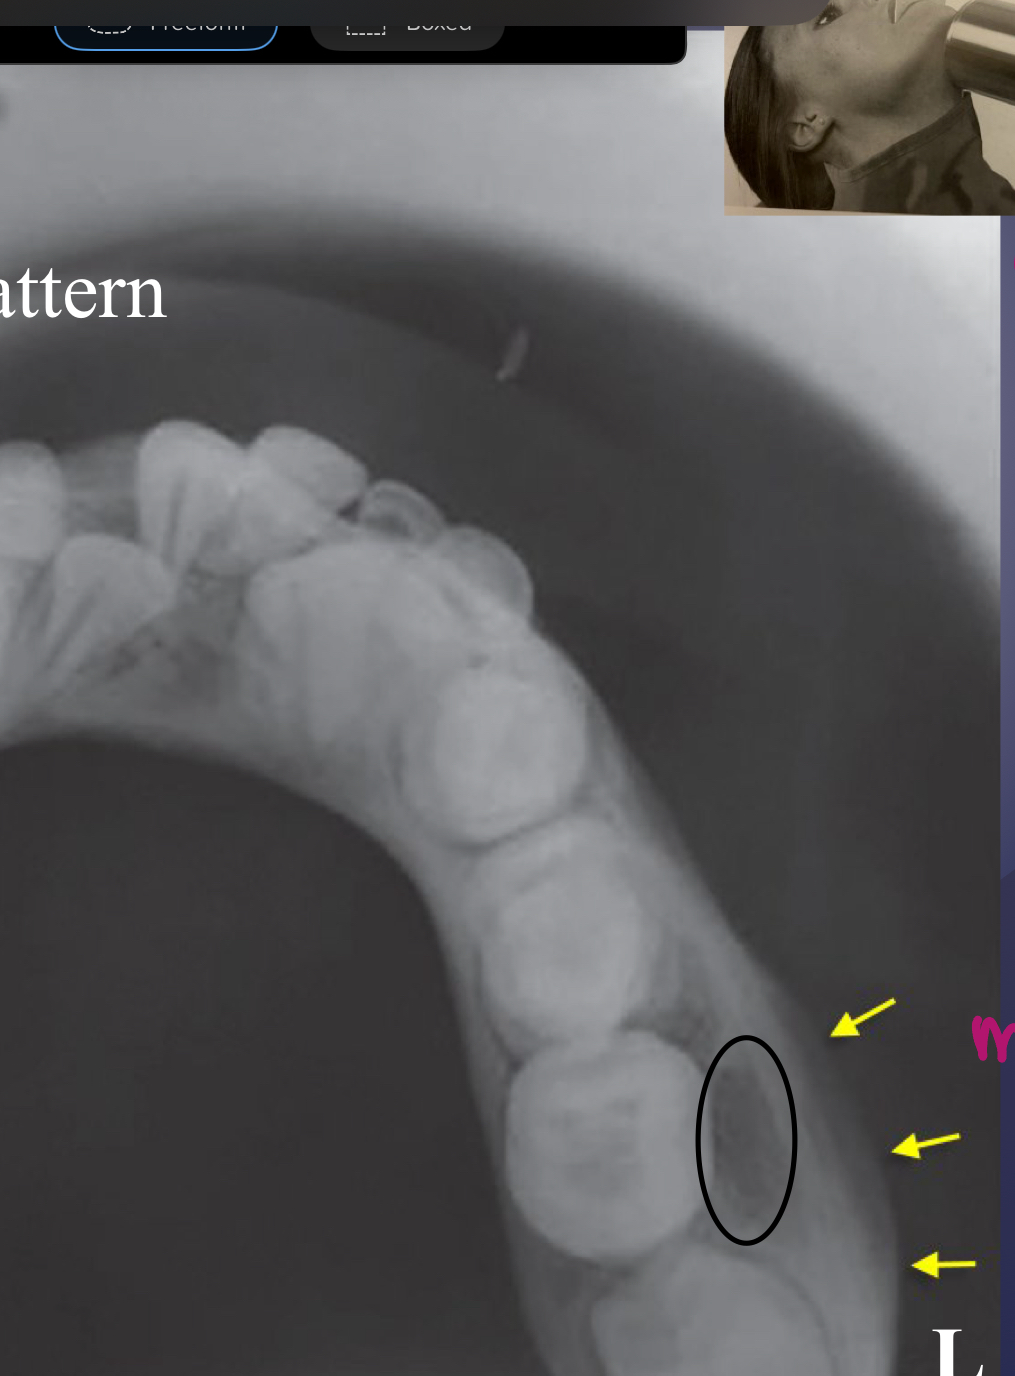

osteomyelitis: periosteal reaction

enlarged follicle is a sign of pericoronitis

false